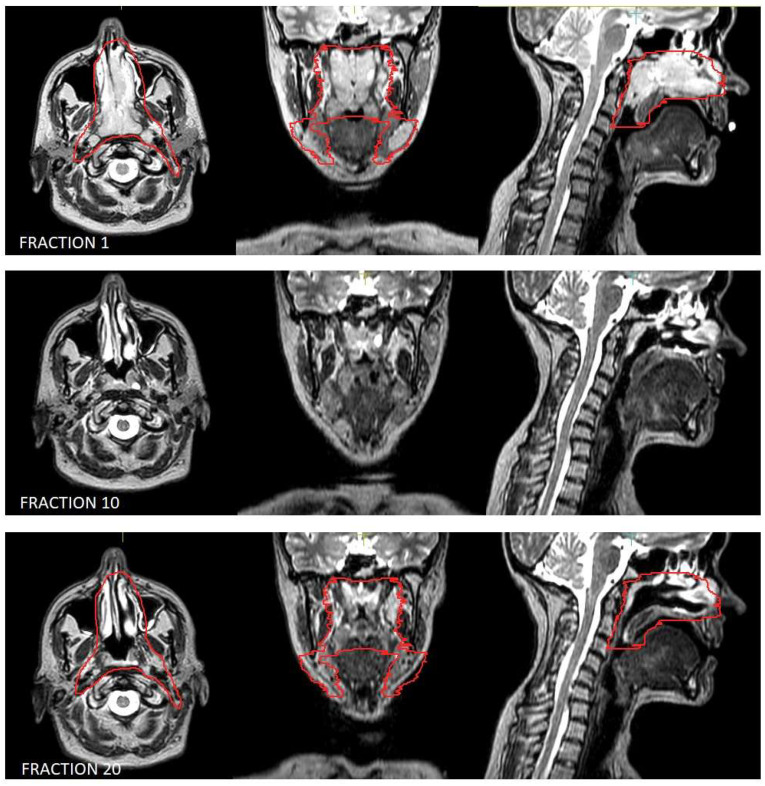

Purpose: Lymphomas are generally radiosensitive; therefore, disease volume tends to shrink during radiotherapy courses. As MRI-linac provides excellent soft tissue definition and allows daily re-contouring of gross tumor volume and clinical target volume, its adoption could be beneficial for the treatment of lymphomas. Nonetheless, at this time there is a lack of literature regarding the use of MR-linac in this context. Methods: A prospective observational study was conducted on patients affected by non-Hodgkin lymphoma (NHL) involving head and neck (H&N) sites and treated with Elekta Unity® MR-Linac. The clinical and dosimetric data of the first eight patients were collected and integrated with relevant data from medical records. Results: Seven patients had B-cell lymphoma (three DLBCL, two MALT, one follicular, and one mantle-cell) and one T-cell/NK lymphoma. The intent of RT was radical for four patients, salvage treatment for three, and CAR-T bridging for one. Two patients presented orbital localizations and six cervical lymphonodal sites. Median GTV was 5.74 cc, median CTV 127.01 cc, and median PTV 210.37 cc. The prescribed dose was 24-50 Gy in 2 Gy fractions for seven patients and 24 Gy in 3 Gy fractions for one patient. All the patients experienced acute toxicity, the maximum grade was G1 for five patients and G2 for three at the end of RT. One month after radiotherapy seven patients still experienced G1 toxicity, but no toxicity grade ≥ 2 was reported. First radiological assessment was performed for all the patients after a median of 101.5 days, reporting complete response in all the cases. After a median follow up of 330 days, no patient experienced local disease progression, while one patient developed distant progression. Conclusions: radiotherapy for NHL with H&N localization using a 1.5 T MR-linac was feasible, with no >G2 toxicity and optimal response rate and disease control.